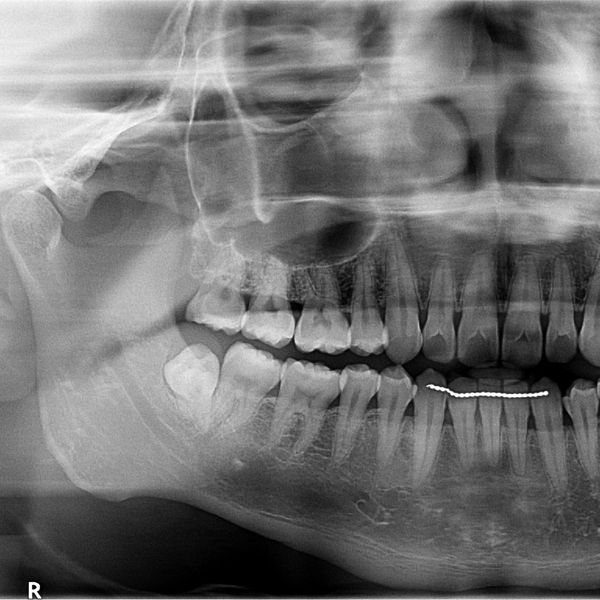

Wisdom teeth, also known as third molars, typically develop between the ages of 17 and 30. While some people may have enough space in their jaw to accommodate these teeth, others may experience pain, swelling, infection, and other complications that require wisdom tooth extraction.